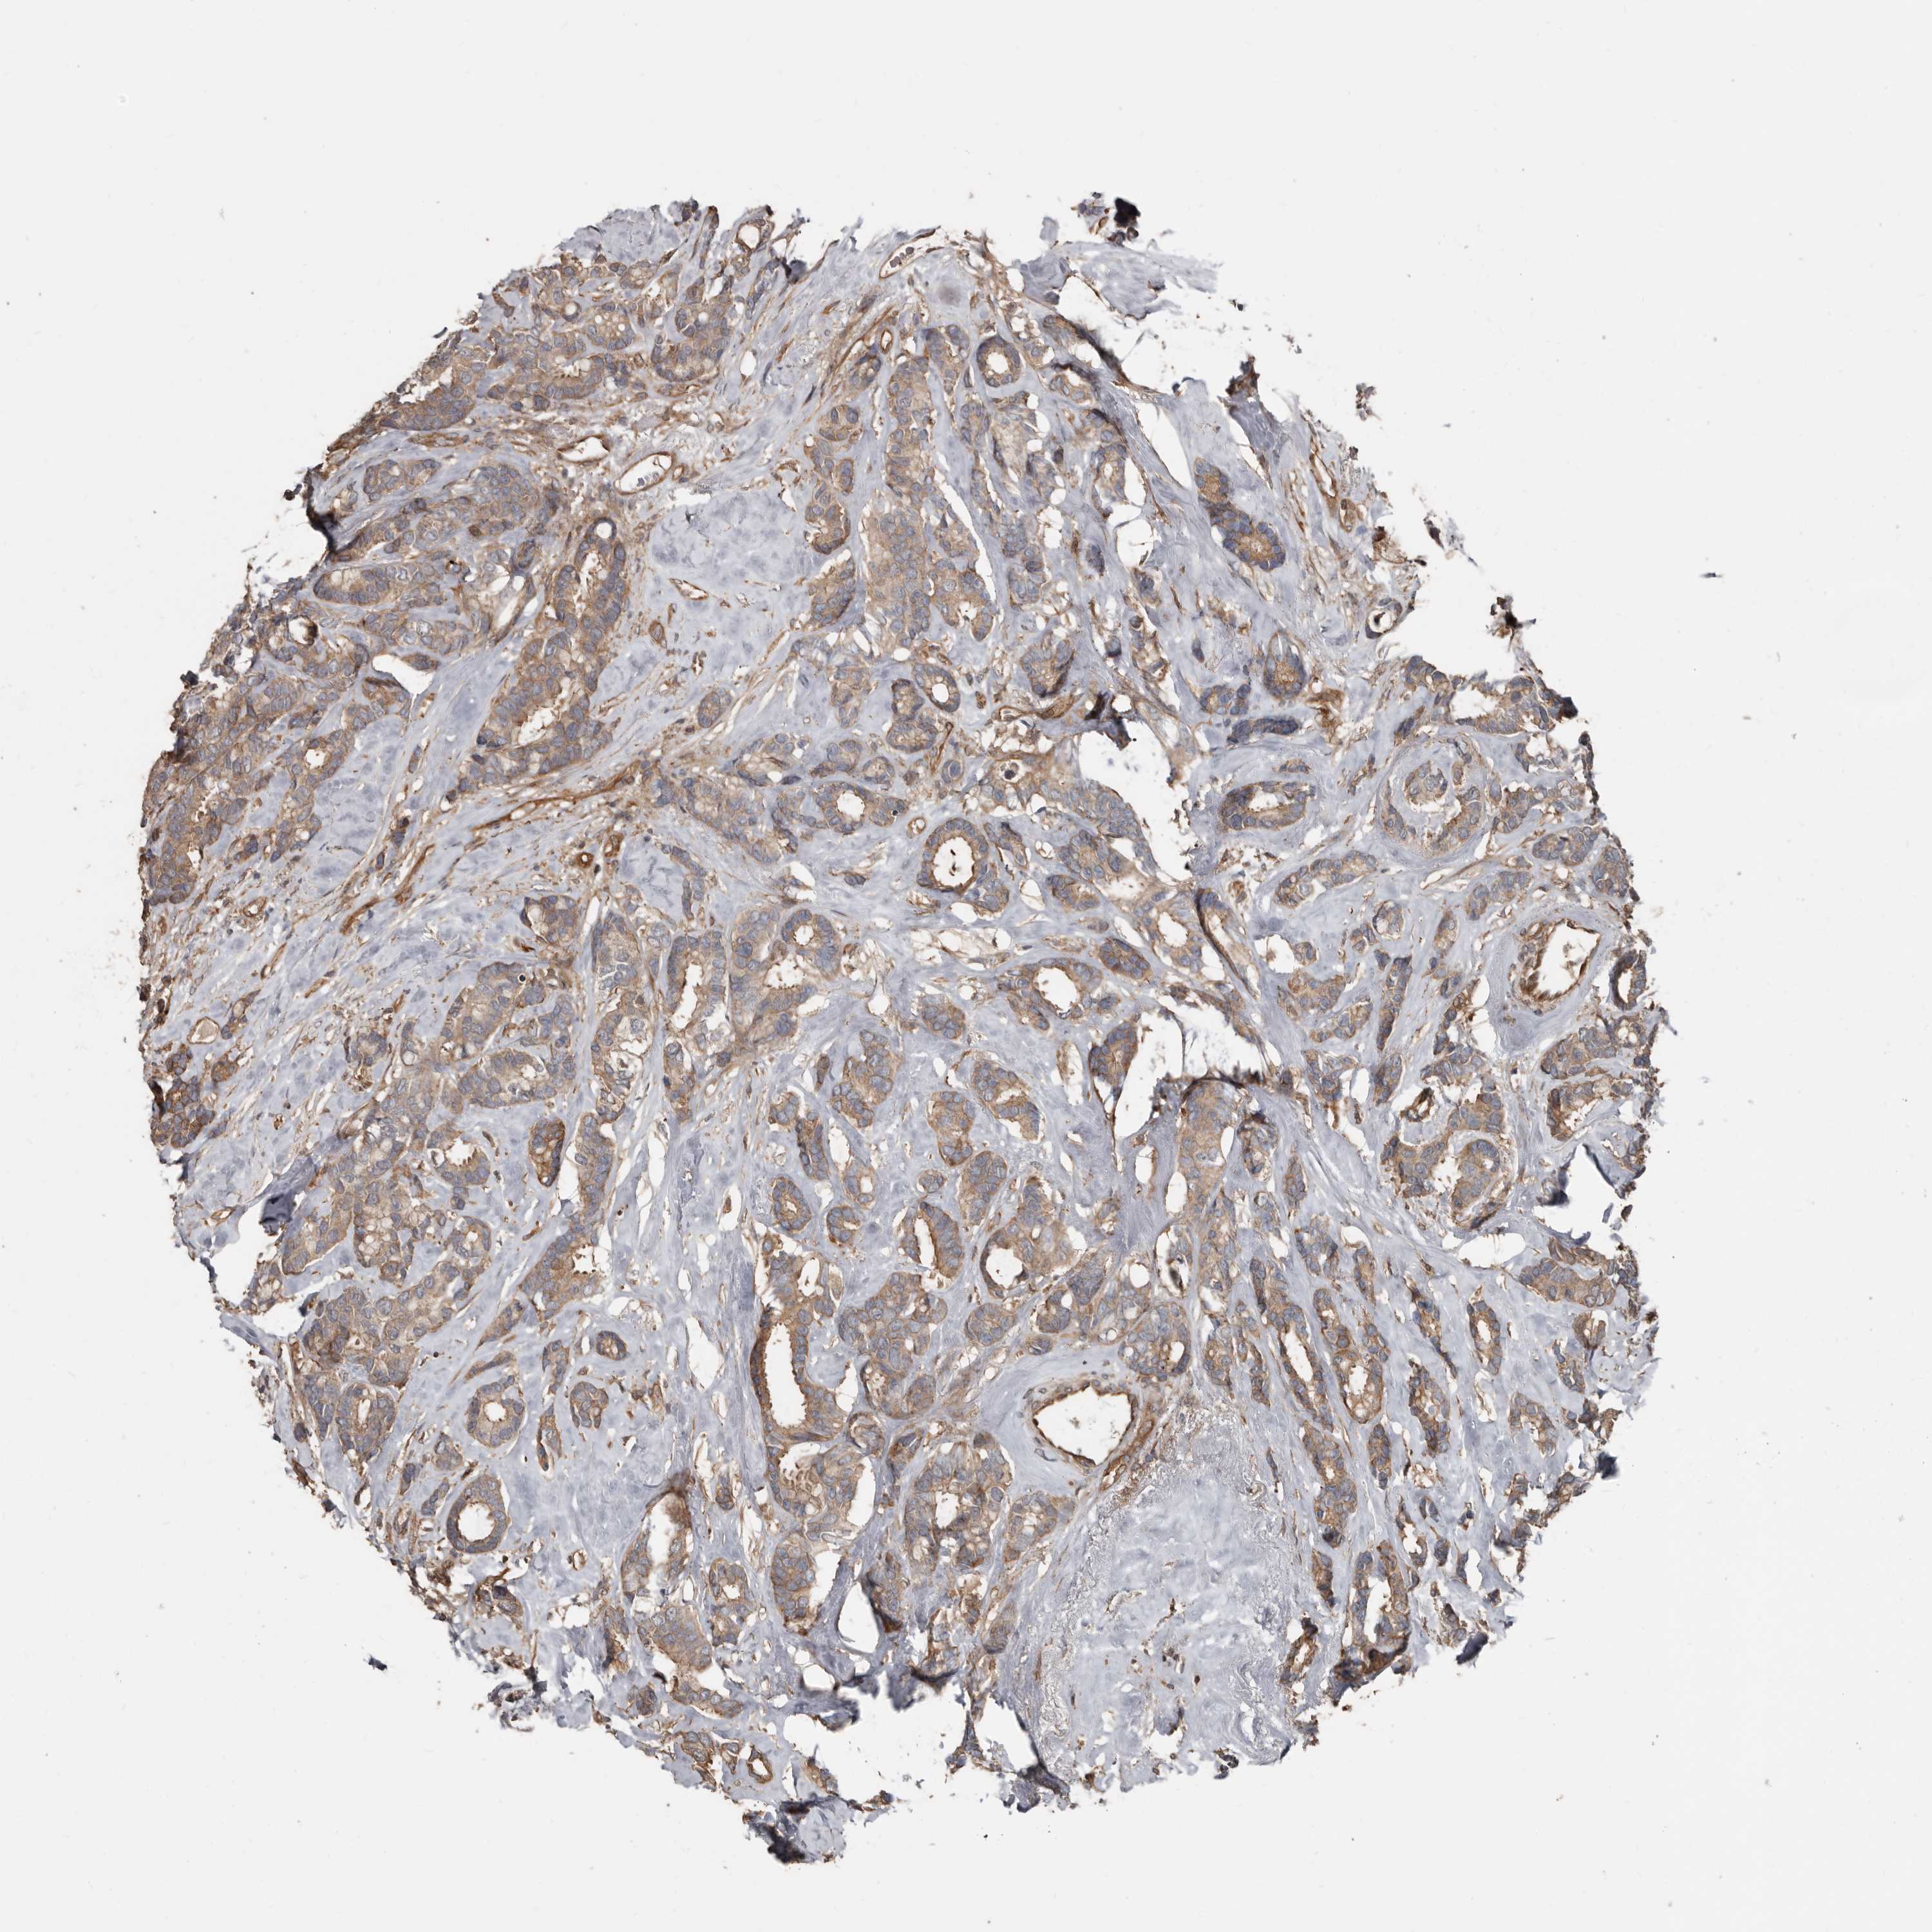

CANCER BREAST CANCER Show tissue menu

BRCA TCGA BRCA VALIDATION PROTEIN EXPRESSION